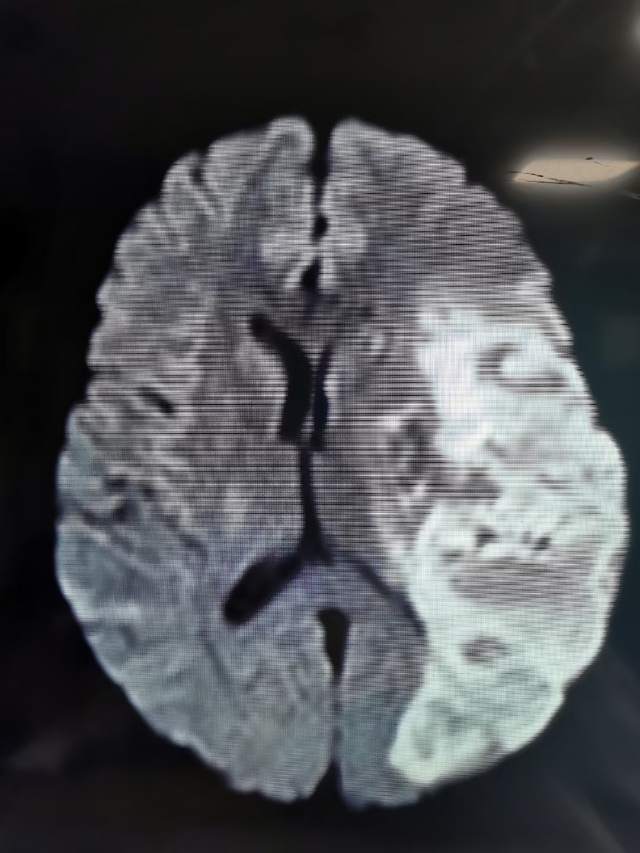

46岁青年女性患者,无高血压和糖尿病病史,突发大面积脑梗塞(图1-2)

遗留右侧肢体残疾,尽管卧床康复3个月,肢体也只能在床上平移,无法抬离床面,完全性失语,不能说话。家属老爸经人介绍辗转收入我科,看看能否得到进一步的改善。第一次晨间病房查房,看到纯朴、善良、苍老的老爸站在床边,向我们不紧不慢的诉说着女儿的病情,年轻秀丽的女儿静静躺在床上,一言不发(完全性失语),想到独生子女家庭在老年突然遭遇失独、残疾等意外后,本是年轻人照顾老年人的季节,现如今却成了白发人弓着背照顾残疾的黑发人,让人心中一阵苍凉和心酸。患者左侧大面积脑梗塞三个月,右侧肢体肌力只有2级,完全性失语;左侧大脑前动脉向左侧大脑中动脉代偿供血,基于上述情况,可能能够做的外科工作并不多,进一步康复的希望也不大。尽管如此,我们还是认真的对患者进行了详尽细致的评估,看看能否找到突破点。造影发现患者颈内动脉起始部存在颈动脉蹼(可能是三个月前引起梗塞的原因,图3)